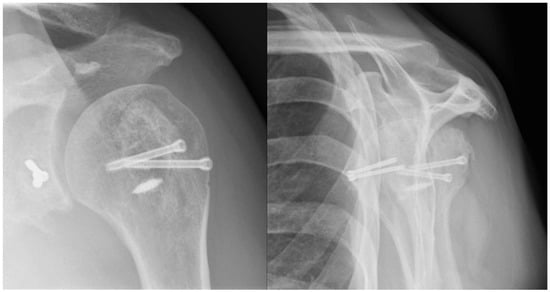

A radiographic assessment revealed an anterior dislocation in the glenohumeral joint, with a concomitant fracture of the greater tuberosity and a Hill-Sachs deformity as shown in Figure 1. The CT scan revealed a bony Bankart lesion of the anterior glenoid rim, and characterized the Hill-Sachs deformity to be large and off-track as shown in Figure 2. Due to the prolonged engagement with the glenoid rim during the 6 weeks that the head was dislocated, a substantial defect was mulled out. A graphic representation of this injury is presented in Figure 3. The patient was scheduled for surgery to be performed in the oncoming days.

Figure 1. Preoperative radiographs. Anteroposterior and lateral “Y-view” radiographs showing the anterior glenohumeral dislocation of the affected shoulder.